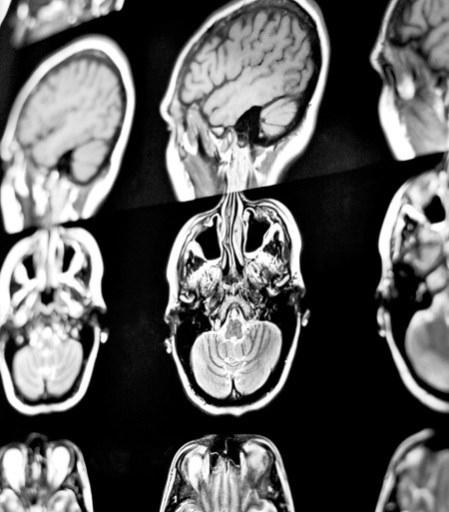

Иллюстрация к книге — Взламывая анатомию [image7.jpg]

Основные анатомические плоскости используются не только в препарировании, но и в медицинской визуализации. Их используют для описания различных проекций тела при проведении компьютерной (КТ) или магнитно-резонансной томографии (МРТ).

Иллюстрация к книге — Взламывая анатомию [image10.jpg]

На этой магнитно-резонансной томограмме (МРТ) изображен мозг. У человека есть несколько органов, без которых он не сможет жить, а мозг является единственным незаменяемым.